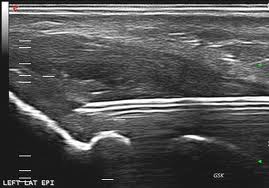

Ευτυχώς τα τελευταία 10-15 έτη έχει σημειωθεί αλματώδης πρόοδος στην Ρευματολογία, τόσο στο διαγνωστικό, όσο και στο θεραπευτικό κομμάτι- δεν είναι τυχαίο ότι μαζί με την Ογκολογία κατέχουν την πρώτη θέση στην εκπόνηση ερευνών παγκοσμίως. Για παράδειγμα, με την χρήση των υπερήχων έχουμε την δυνατότητα πρώιμα και αξιόπιστα να ελέγχουμε αρθρώσεις και περιαρθρικούς ιστούς για φλεγμονώδεις ή/και εκφυλιστικές καταστάσεις, ενώ δίνεται και η δυνατότητα να παρέμβουμε θεραπευτικά με κατευθυνόμενες παρακεντήσεις και εγχύσεις. Επίσης, νεότερα φάρμακα που αναπτύχθηκαν με βάση την κατανόηση των παθογενετικών μηχανισμών των ρευματικών νοσημάτων δίνουν την δυνατότητα για πρώιμη αντιμετώπιση, πριν παρουσιαστούν μη αναστρέψιμες βλάβες.